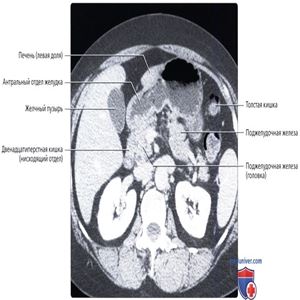

КТ с контрастированием: нормальное взаиморасположение желудка и прилегающих органов. Обратите внимание, что желудок может быть сдавлен увеличенной печенью или селезенкой.

Обратите внимание на малый сальник, содержащий жировую ткань, сосуды и лимфатические узлы желудка и печени.

Верхняя стенка желудка прилежит к поджелудочной железе, между ними расположен только малый сальник. Желчный пузырь прилежит к антральному отделу желудка и луковице двенадцатиперстной кишки. Большая кривизна желудка касается селезеночного изгиба толстой кишки.

Антральный отдел желудка прилежит к головке поджелудочной железы кзади и желчному пузырю сбоку.